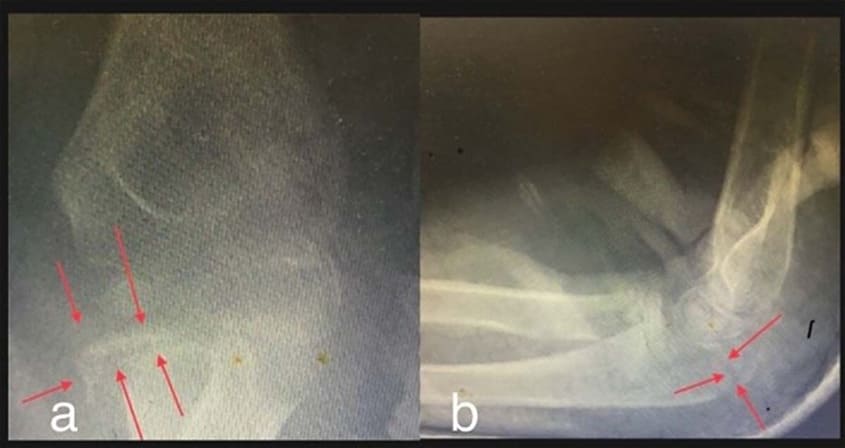

Figure 1: Elbow radiograph in two different incidents. Front and lateral standard images could not be obtained due to the patient’s antalgic attitude and agitation. In this situation, only sedation or anaesthesia allows capturing standard images. Posterior radial head dislocation is evident in both pictures. TRASH injuries are suspected at the elbow.

Figure 2: The control radiograph taken through the cast shows reduction of the radial head and suggests an ulnar fracture and three possible lesions: Salter-Harris type II radial head fracture, capitellum fracture or coronoid fracture.